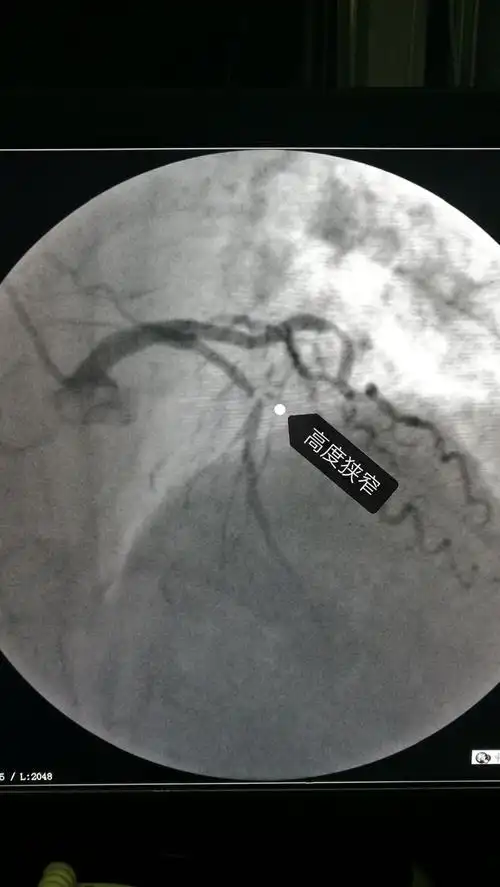

冠脉造影示:前降支中段100%闭塞,为此次心肌梗死之罪犯血管

急诊手术,造影发现前降支严重狭窄,血流明显减慢